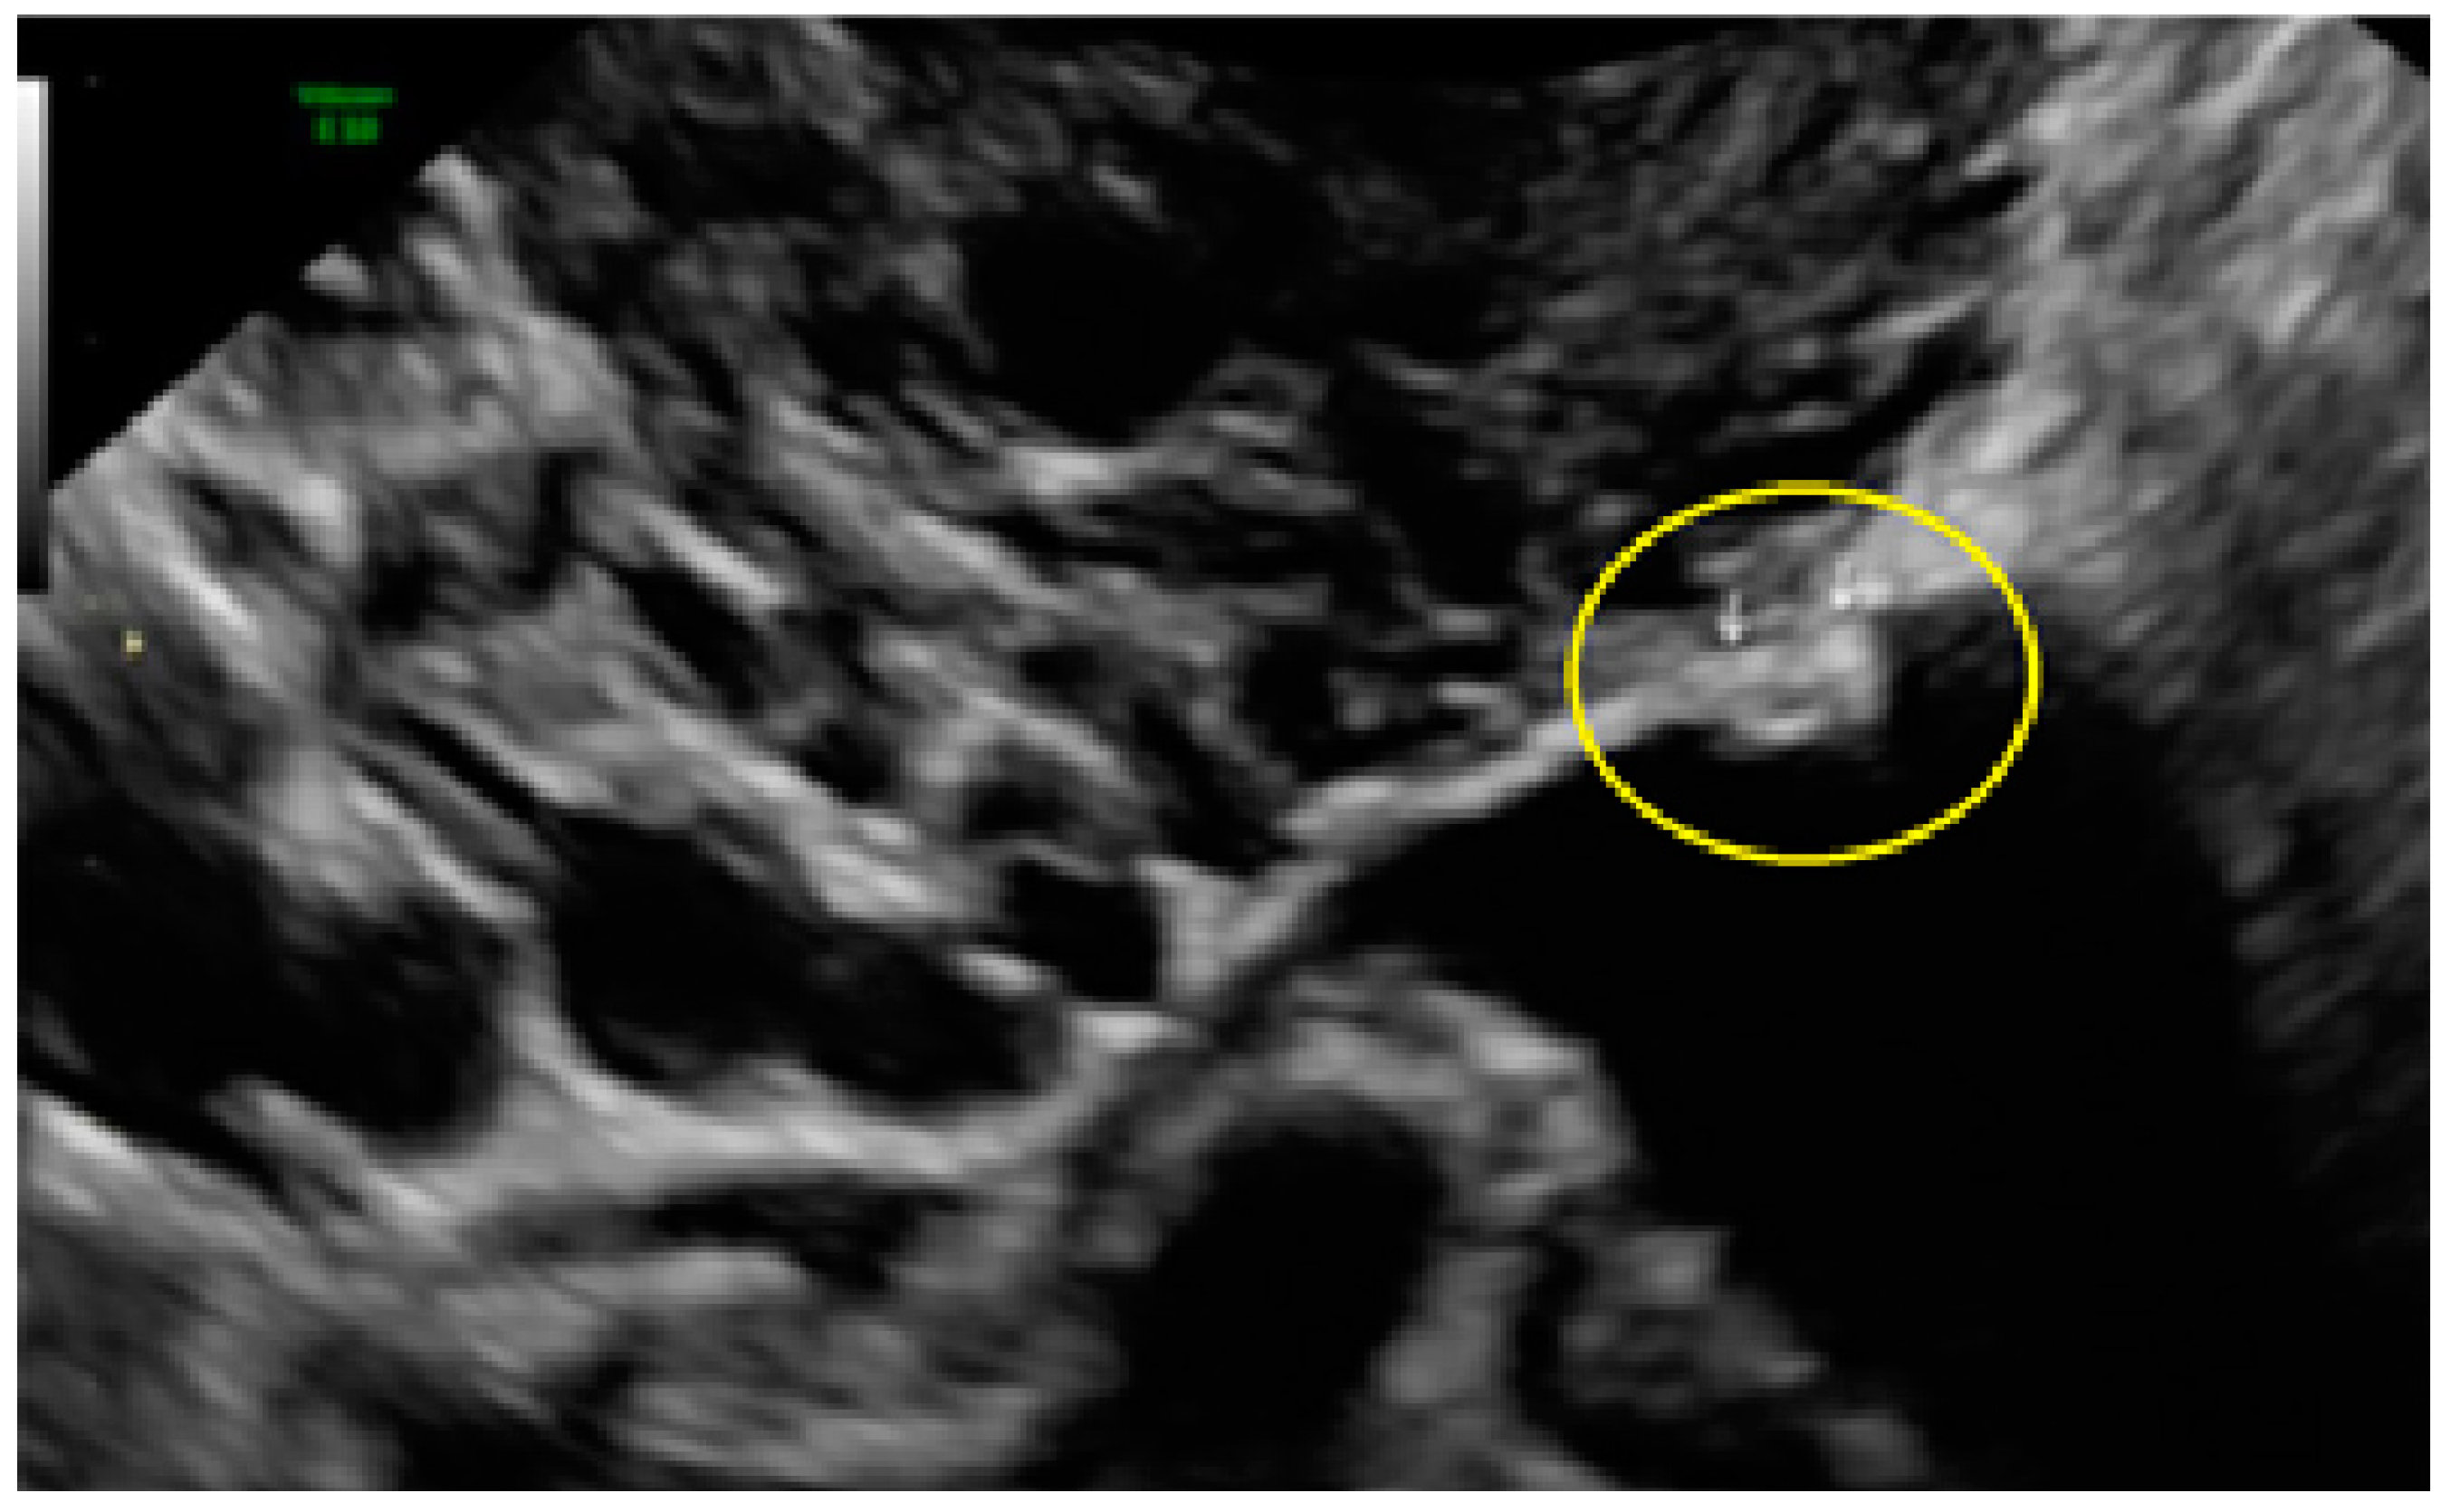

- The lesion may be convex, protruding from the peritoneal surface into the peritoneal cavity (we called this “bulging”), or it may appear as a concave defect in the peritoneum (we called this a “pocket”).

- The presence of hyperechoic foci (we called this a “pearl”).

- The presence of velamentous (filmy) adhesions associated to the lesion (we called this a “veil”).

3.3. Cystic Lesions Arranged in a Cluster